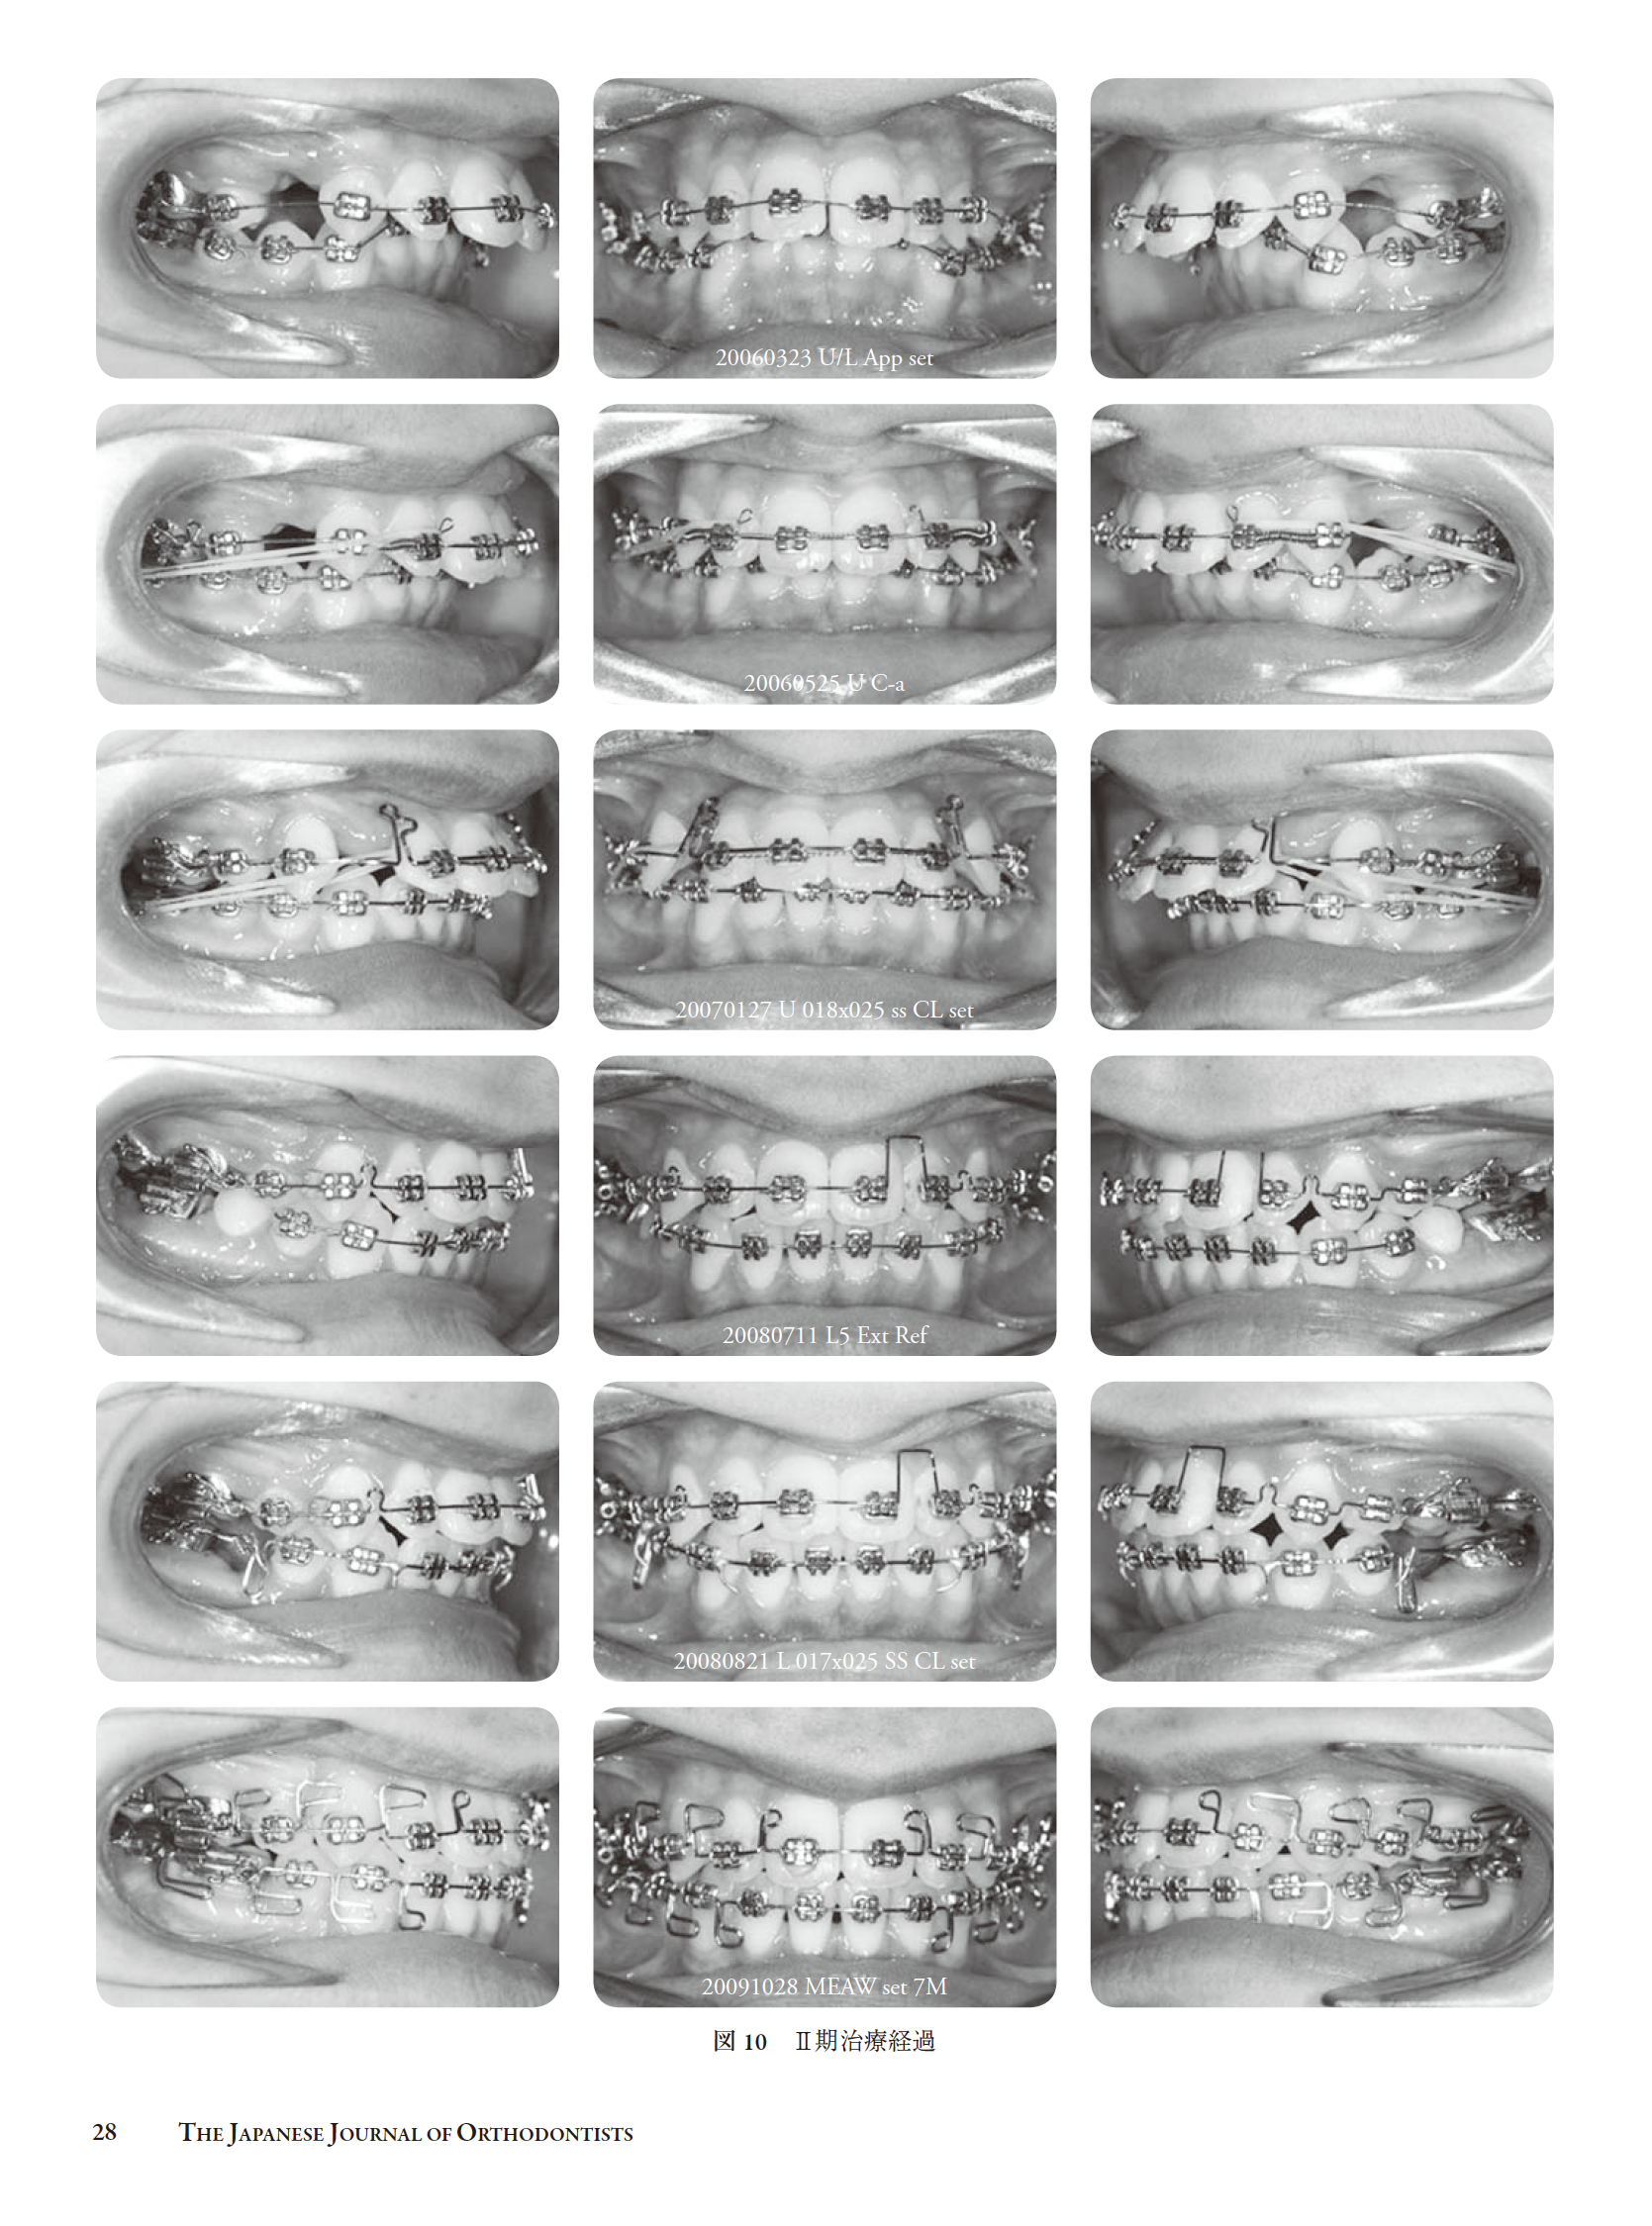

混合歯列期における上突咬合を振り返って(和島)